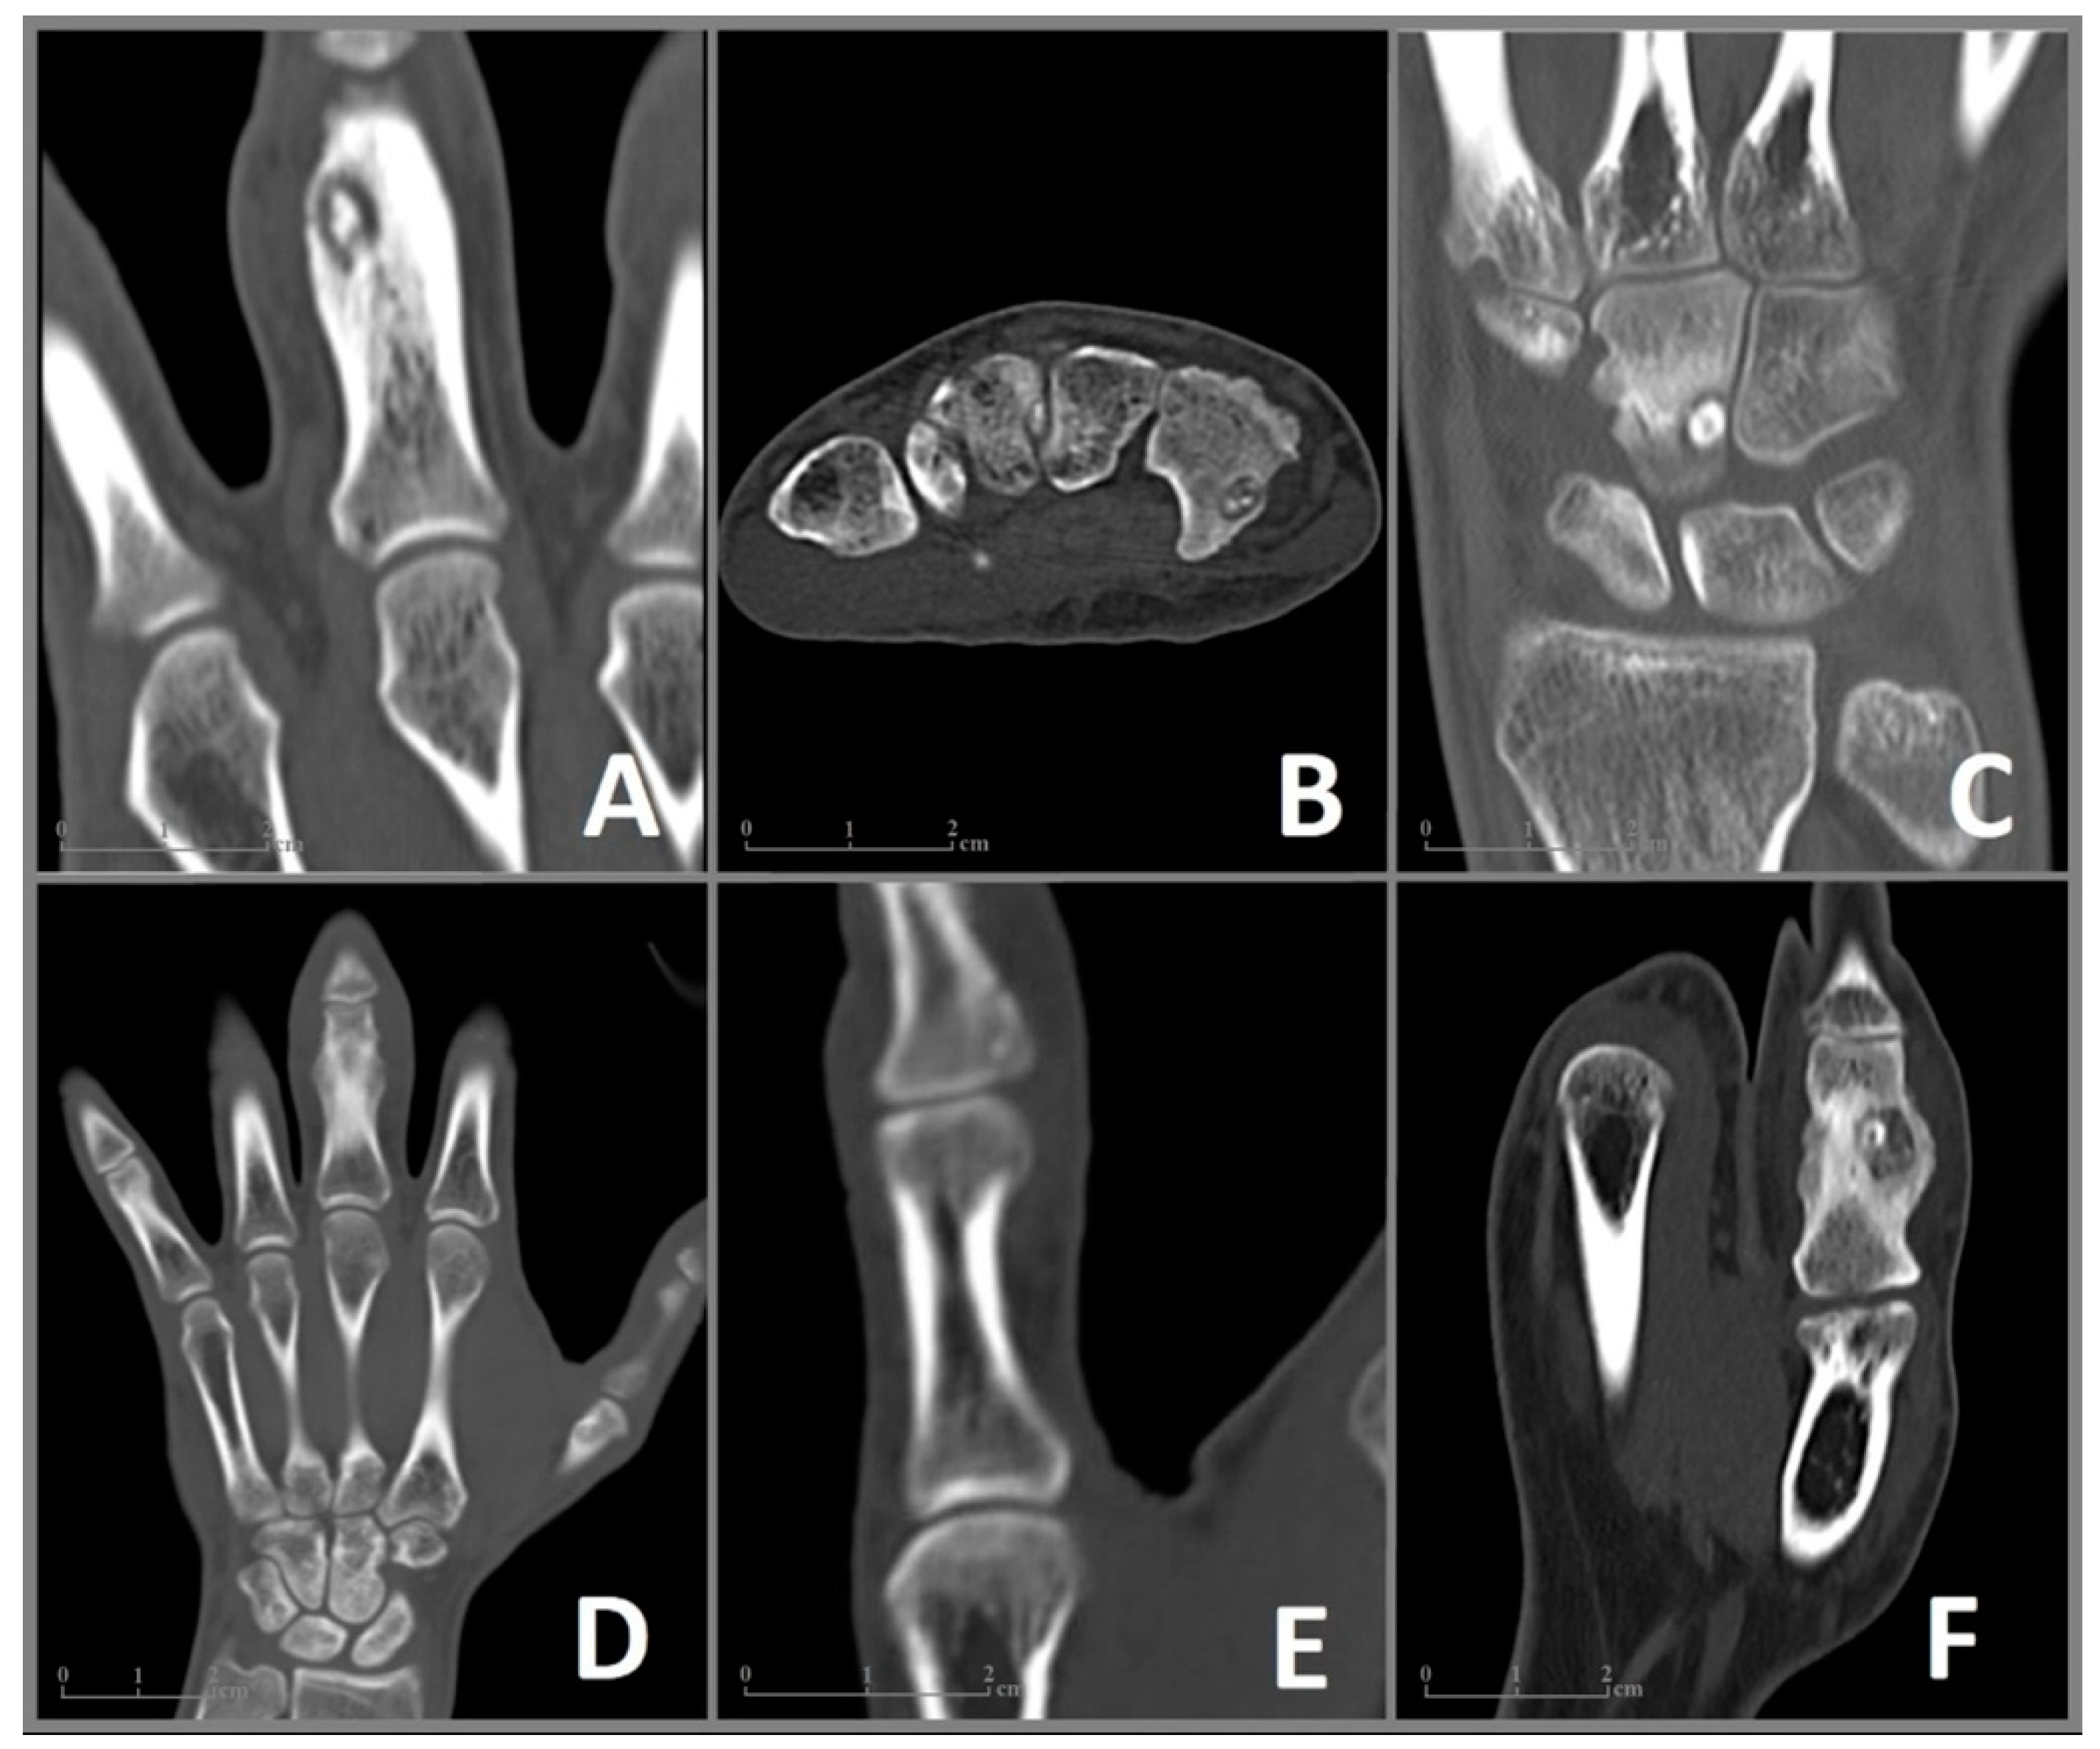

Figure 2.

CT imaging of the included cases 1–6 (A–F) of OO in the bones of the hand. (A) Case 1: Coronal CT image showing a nidus with a diameter of 9 × 6 mm and surrounding sclerosis in the proximal phalanx of the left middle finger. (B) Case 2: Axial CT image of a 6 × 4 mm nidus in the hook of the hamate. (C) Case 3: Coronal CT image revealing a juxta-articular nidus (7 × 5 mm) at the ulnar surface of the capitate. (D) Case 4: Coronal CT image showing enlargement and deformation in the proximal phalanx of the middle finger. The nidus (10 × 7 mm) is difficult to distinguish. (E) Case 5: Coronal CT Image of a 6 mm nidus in the distal phalanx in close proximity to the interphalangeal joint. (F) Case 6: Coronal CT image showing a 9 × 8 mm nidus in the proximal phalanx of the thumb with pronounced sclerosis as well as deformation and enlargement of the affected bone.

In June 2006, a 35-year-old male patient presented to our clinic with pain and enlargement of the proximal phalanx of the left middle finger. He was right-handed and had no motoric deficits in the adjacent joints of the affected finger. The following X-ray revealed a bony lesion adjacent to the cortical bone with a strong periosteal reaction in the proximal phalanx. An open biopsy was performed. Due to the clinical presentation and histological assessment of the biopsy, Nora’s lesion was suspected. The patient received regular clinical and radiographic monitoring. In 2007 an X-ray showed a complete regression of the lesion after the biopsy. Due to permanent pain and swelling with limitations at work, MRI (Figure 1A) and CT (Figure 2A) were performed in 2009, which revealed an intracortical nidus (diameter 9 mm) in the proximal phalanx, deformity of the affected bone and edema of the surrounding tissue in MRI. In August 2010, the lesion was removed en bloc through a mid-lateral approach. The defect was filled with a bone graft from the ipsilateral iliac crest and stabilized with three tension screws. In the following histological assessment, OO was confirmed. During follow-up examinations, the patient was free of pain with a slight limitation of flexion of 5 degrees in the proximal interphalangeal joint.

A 27-year-old right-handed man complained of pain in his right wrist without trauma for 7 months. The pain intensified at night and did not improve significantly with NSAID. The clinical presentation revealed tenderness of palpation over the ulnar wrist as well as pain in full extension and flection without movement restrictions. There was no swelling, deformities, or previous operations in anamnesis. An MRI (Figure 1B) performed in January and March 2020 showed excessive marrow edema in the hamate and the surrounding soft tissue. An X-ray in February 2020 showed no abnormalities in the wrists pictured. With the diagnosis of tendinitis due to overuse, the wrist was immobilized for several weeks at a peripheral outpatient clinic. The pain increased despite immobilization, and the follow-up examination showed a demineralization of the hamate. A CT scan in June 2020 (Figure 2B) revealed an intracortical nidus in the hook of the hamate with a diameter of 6 mm. As OO was suspected, the patient was referred to our clinic for surgical treatment. We performed open curettage via incision above Guyon’s canal in November 2020 (Figure 3). The defect was filled with cancellous bone from the ipsilateral distal radius. Histological analysis confirmed the diagnosis of OO (Figure 4). During the follow-up examination, the patient showed a significant decrease in pain and no motor restrictions with complete remineralization of the hamate.

In January 2020, a 22-year-old male patient was referred to our clinic for the excision of an unclear tumor in the capitate of the left hand. The right-handed patient described pain in his left wrist, which had increased in the last 1.5 years. The examination showed tenderness of palpation over the wrist with painful movement restrictions in flexion and extension without local swelling. Supination and pronation were without limitations. An MRI in August 2019 (Figure 1C) revealed a small lesion in the capitate surrounded by an excessive bone marrow edema in the capitate, the hamate, the surrounding carpal joints, and the soft tissue of the dorsal wrist, including the synovial sheath of the dorsal tendon. A CT scan performed in October 2019 (Figure 2C) showed a juxta-articular lesion with a diameter of 7 mm and regional destruction of the surrounding dorsolateral cortical bone. OO was suspected. Due to pain and movement restrictions, the indication of local excision of the tumor was provided. In January 2021, an open curettage with a subsequent filling of the defect with cancellous bone from the distal radius was performed through a dorsal approach. Due to the risk of postoperative instability of the amphiarthrosis between the capitate and hamate, a temporary arthrodesis was performed using K-wires. Histological analysis confirmed the diagnosis of a subchondral OO. After surgery, the patient was free of pain with good mobility in the wrist and a slight local swelling in a four-month follow-up examination.

A 27-year-old man was referred to our clinic due to painful swelling of the lower part of the middle finger of his left hand, including the proximal interphalangeal joint, for a 12-month duration. The swelling led to movement restrictions in the joints of the affected finger. An MRI in March 2019 (Figure 1D) revealed a bone marrow edema in the distal phalanx and the surrounding palmar soft tissue. An orthopedist initially ruled out a rheumatic disease. Subsequently, the patient was treated antibiotically due to the detection of antibodies against the borrelia antigen. Due to permanent pain and swelling, a CT scan (Figure 2D) was performed, which showed juxta-articular osteolysis with surrounding sclerosis. A biopsy performed in the same month showed no evidence of bacterial inflammation, and no histological diagnosis could be secured. We opted for a complete resection of the tumor with open curettage via palmar access. Histological analysis confirmed the diagnosis of an OO. The patient was free of pain without movement restrictions in the follow-up examination.

A 24-year-old male patient reported enlargement and pain in the distal phalanx of the right thump for more than one year. The pain was dominant at nighttime and responded to NSAID. The clinical examination revealed local tenderness on palpation, no movement restrictions, and a deformity of the right thump with hypertrophy of the nail. Circular osteolysis at the base of the distal phalanx was initially detected in the X-ray. Osteitis was suspected, and the patient received oral antibiotics for 2 weeks and immobilization of the finger. Due to permanent pain, an MRI and CT were performed in November 2011 (Figure 1E and Figure 2E), which revealed a bone marrow edema and a small intracortical nidus close to the base of the distal phalanx. OO was suggested, and the patient introduced himself for the local resection in our clinic. We performed an open curettage via a mid-lateral incision. The patient was free of pain in follow-up examinations.

A 29-year-old left-handed male patient was admitted to our outpatient clinic with a 12-month history of pain responding to ibuprofen and swelling of the proximal phalanx of the left thumb. There were movement restrictions in the metacarpophalangeal and interphalangeal joints of the thumb. An MRI in October 2019 (Figure 1F) revealed a bone marrow edema of the proximal phalanx as well as an intracortical nidus with a reaction of the adjacent periost. The additional CT (Figure 2F) confirmed the nidus, measuring about 9 mm in size, surrounded by dense reactive bone with enlargement of the middle phalanx. A primary bone tumor (differential diagnosis osteomyelitis) was suspected. An open curettage through a mid-lateral dorsal approach with removal of sclerosis revealed brown cancellous bone. OO was histologically confirmed. The patient has remained symptom-free at the follow-up evaluation.